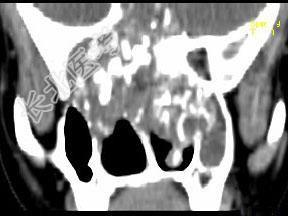

- 单项选择题男,26岁, 进行性鼻腔阻塞、流涕来院就诊,近两年持续性头痛、头晕, 筛窦区病变影像检查如图,最可能的诊断是 ( )